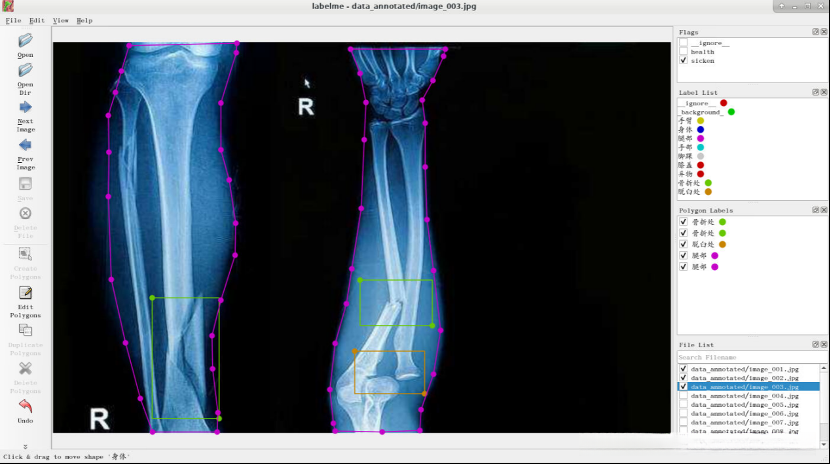

由于结果图片过多,仅展示部分图片。

任务实施过程

- 使用labelme进行图像标注

观察图像,判断患者是否健康,认为该患者是健康的,所以flag选择“health”。

请在电子图像中识别出人体关键部位,并通过右键点击执行"Create Polygons"操作。

左键点击图片,将图像中的手臂标注出来,选择相应的label,然后点击OK。

点击OK后,结果如下图所示。

10.点击“Next Image”,将图像中人是否是健康的,无法判定时选择“ignore ”。

将图像中人体标注出来并选择相应的label。

点击“Next Image”,判断健康状况并选择相应的flag。